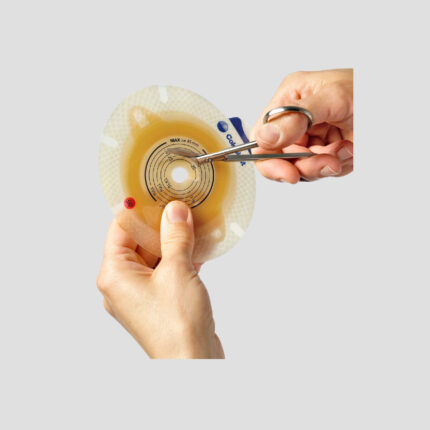

SenSura® Mio 2-Piece Transparent Bag for Urostomy

All-in-one colostomy/ileostomy appliance for maximum discretion.

Spiral adhesive for security and skin friendliness. Alterna 1-piece drainable features the unique skin-friendly spiral adhesive.

| Diameter |

50 mm ,60 mm |